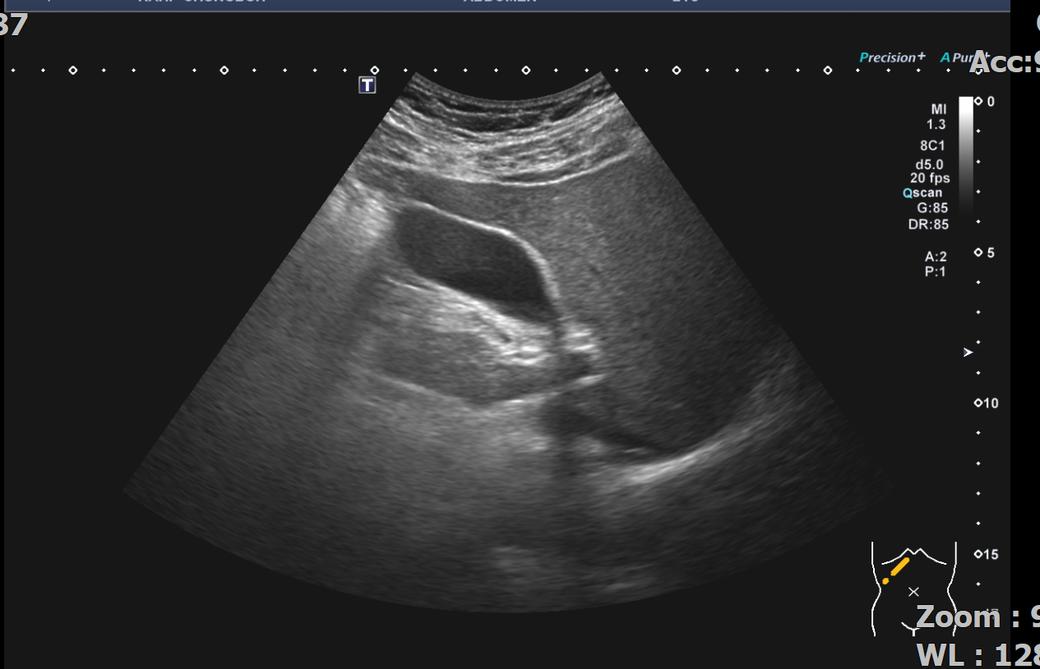

뭐가보이나요? 부위 사진 캡쳐하고 4장 같은부위 촬영사진 올려요

• 3번 째 사진

맨 위 사진의 위치에서는 probe를 tilting을 하면 신장이 보이기는 하지만

그 보다는 신장의 관찰을 위해서 probe를 조금더 아래 level로 가지고 갑니다.